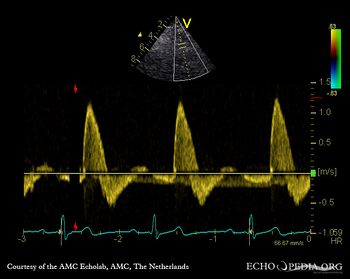

E00231.gif E00232.gif

PLAX: prolapse of aortic valve PLAX: Color Doppler severe aortic regurgitation, eccentric jet